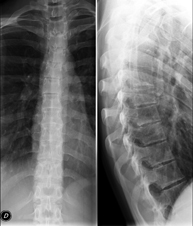

Técnica mediante la cual, utilizando rayos X, se obtienen imágenes de la columna cervical para su estudio. Indicaciones: traumatismo, dolor cervical. - RX Columna dorsal

Técnica mediante la cual, utilizando rayos X, se obtienen imágenes de la columna dorsal para su estudio. Indicaciones: traumatismo, dolor de espalda. - RX Columna lumbar

Técnica mediante la cual, utilizando rayos X, se obtienen imágenes de la columna lumbar para su estudio. Indicaciones: ciática, traumatismo, dolor lumbar. - RX Sacro-cóccix

Técnica mediante la cual, utilizando rayos X, se obtienen imágenes del sacro y del cóccix para su estudio. Indicaciones: traumatismo, dolor sacro o coccígeo. - Telerradiología columna

Técnica mediante la cual, utilizando rayos X, se obtienen imágenes de toda la columna vertebral para su estudio, valorando especialmente la presencia de escoliosis y dismetrías pélvicas.